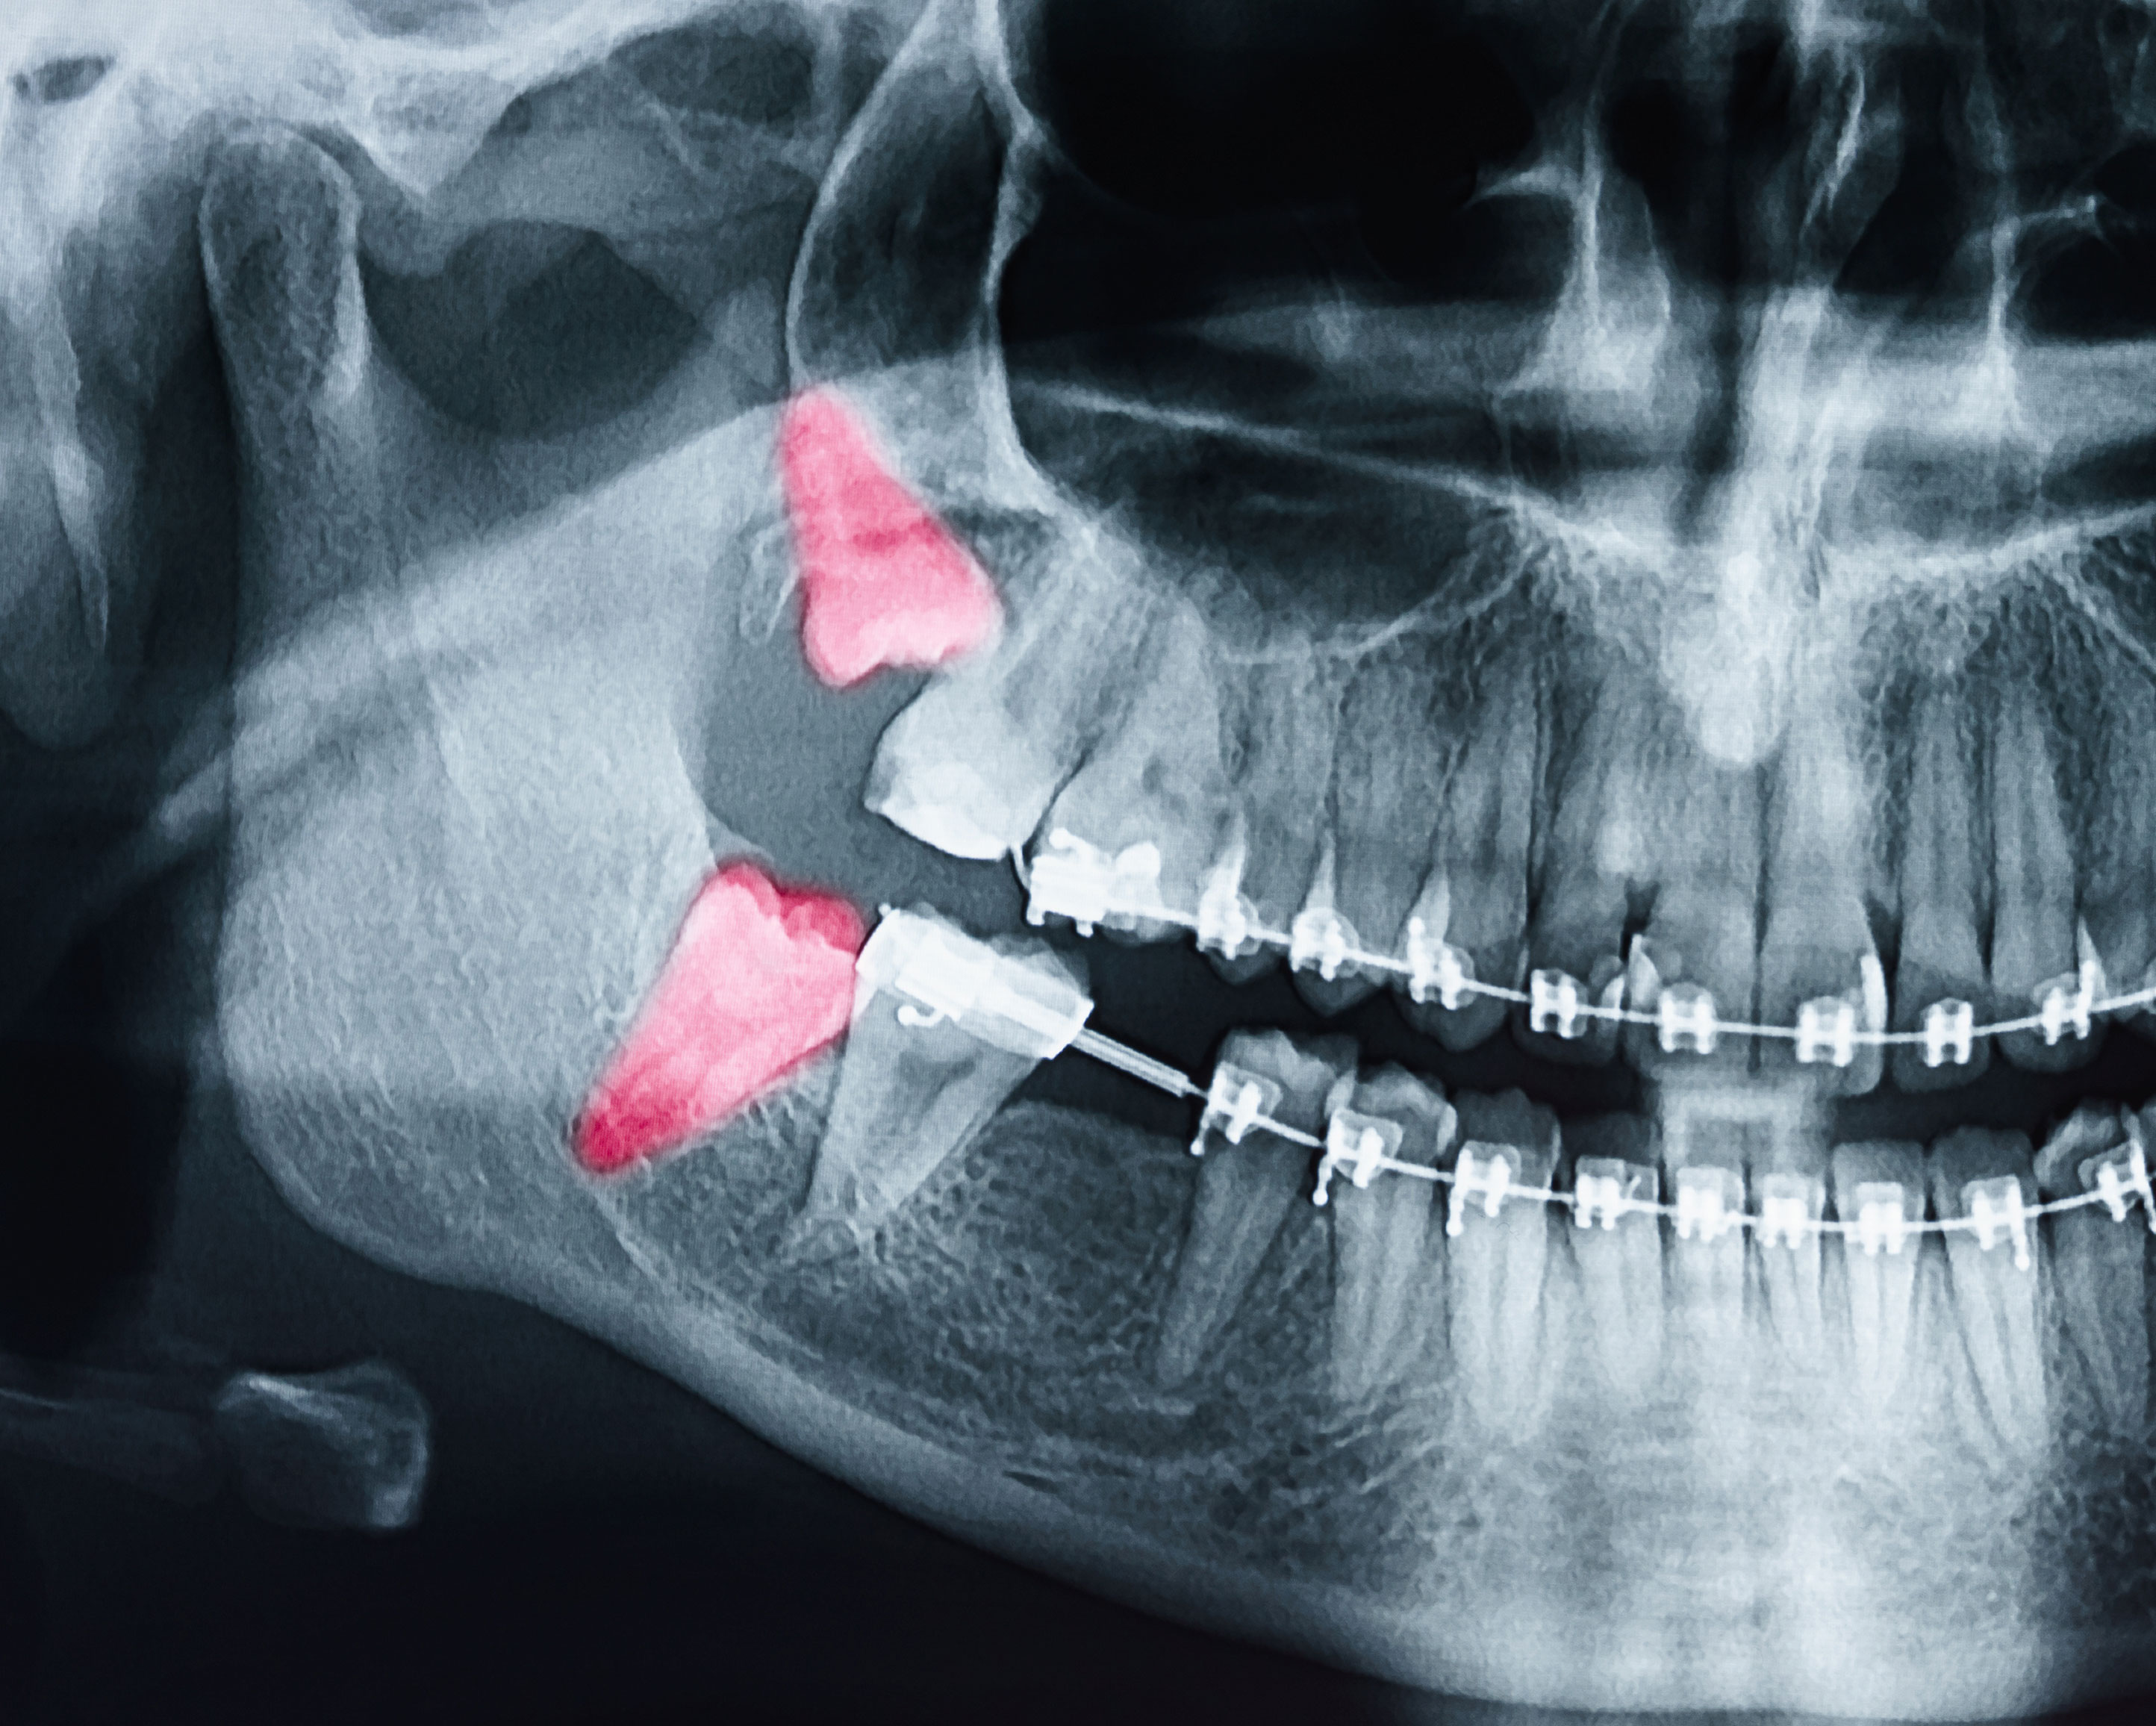

Miramar Beach Oral Surgery Services

Oral Surgeon in Miramar Beach